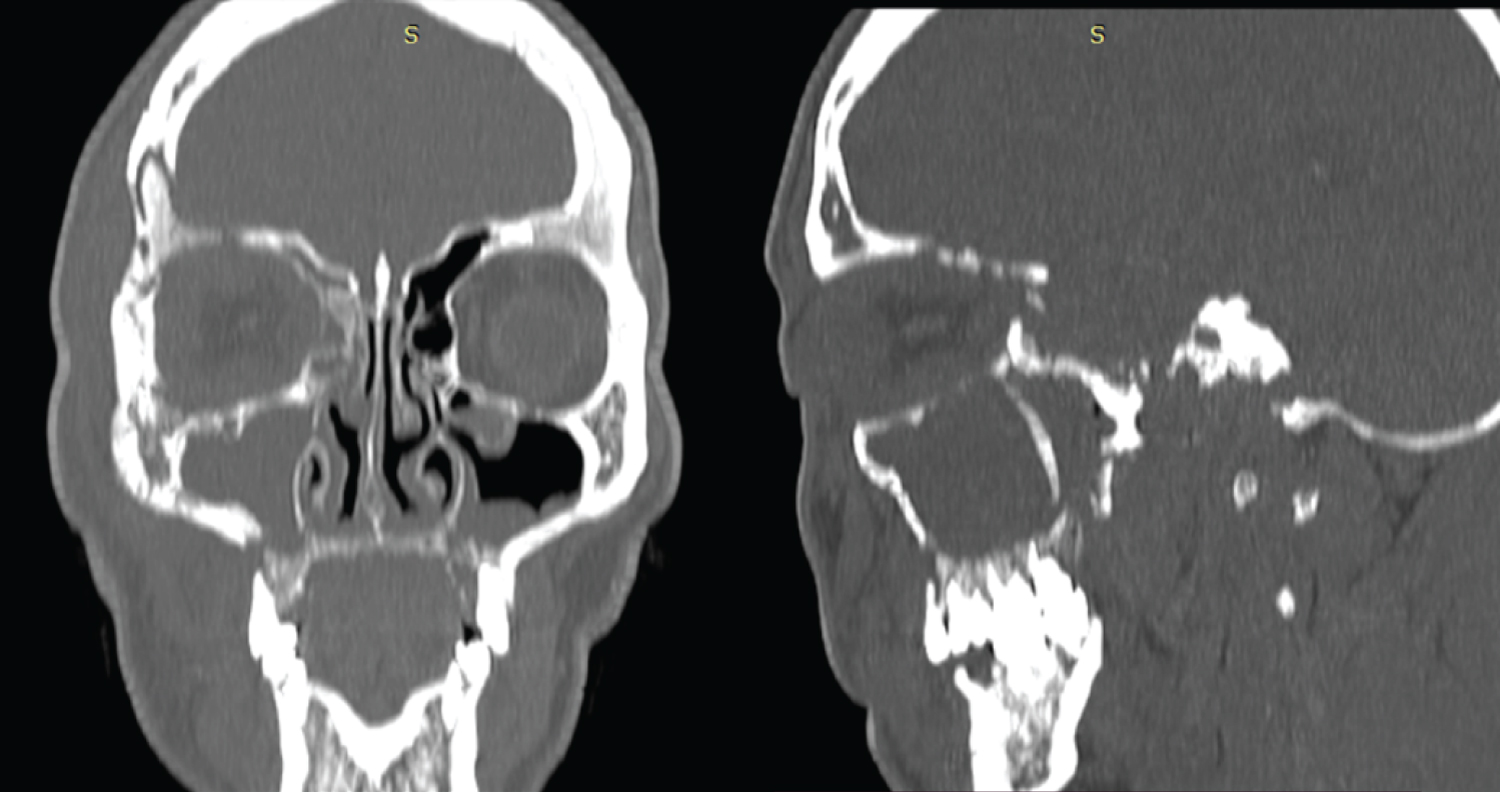

This paper reports the case of a 51-year-old male patient who attend to the Maxillofacial Surgery service of the University Hospital of Maracaibo with a diagnosis of Rhinocerebral mucormycosis with 4 months of evolution with a history of type II diabetes mellitus and survivor of Covid 19. Clinical Extraoral examination showed volume increase in the right orbital region with total palpebral occlusion, fluctuating on palpation, non-reactive right pupil, loss of vision, ophthalmoplegia, chemosis and ipsilateral proptosis (Figure 1). Intraoral clinical examination evidenced mobility of the anterior and lateral segment on the right side of the maxilla. The imaging examination through CT of the Face showed changes in the densities of the Maxilla compatible with bone resorption that extended to the walls of the orbit and temporal bone on the right side. Mucosal thickening of the bilateral maxillary sinus, obstruction of the osteomeatal complex and involvement of the sphenoid sinus were observed (Figure 2). Clinical and imaging findings confirmed unilateral cavernous sinus thrombosis.

Figure 2: TC show changes in the densities of the maxilla compatible with bone resorption that extended to the walls of the orbit and temporal bone on the right side. View Figure 2